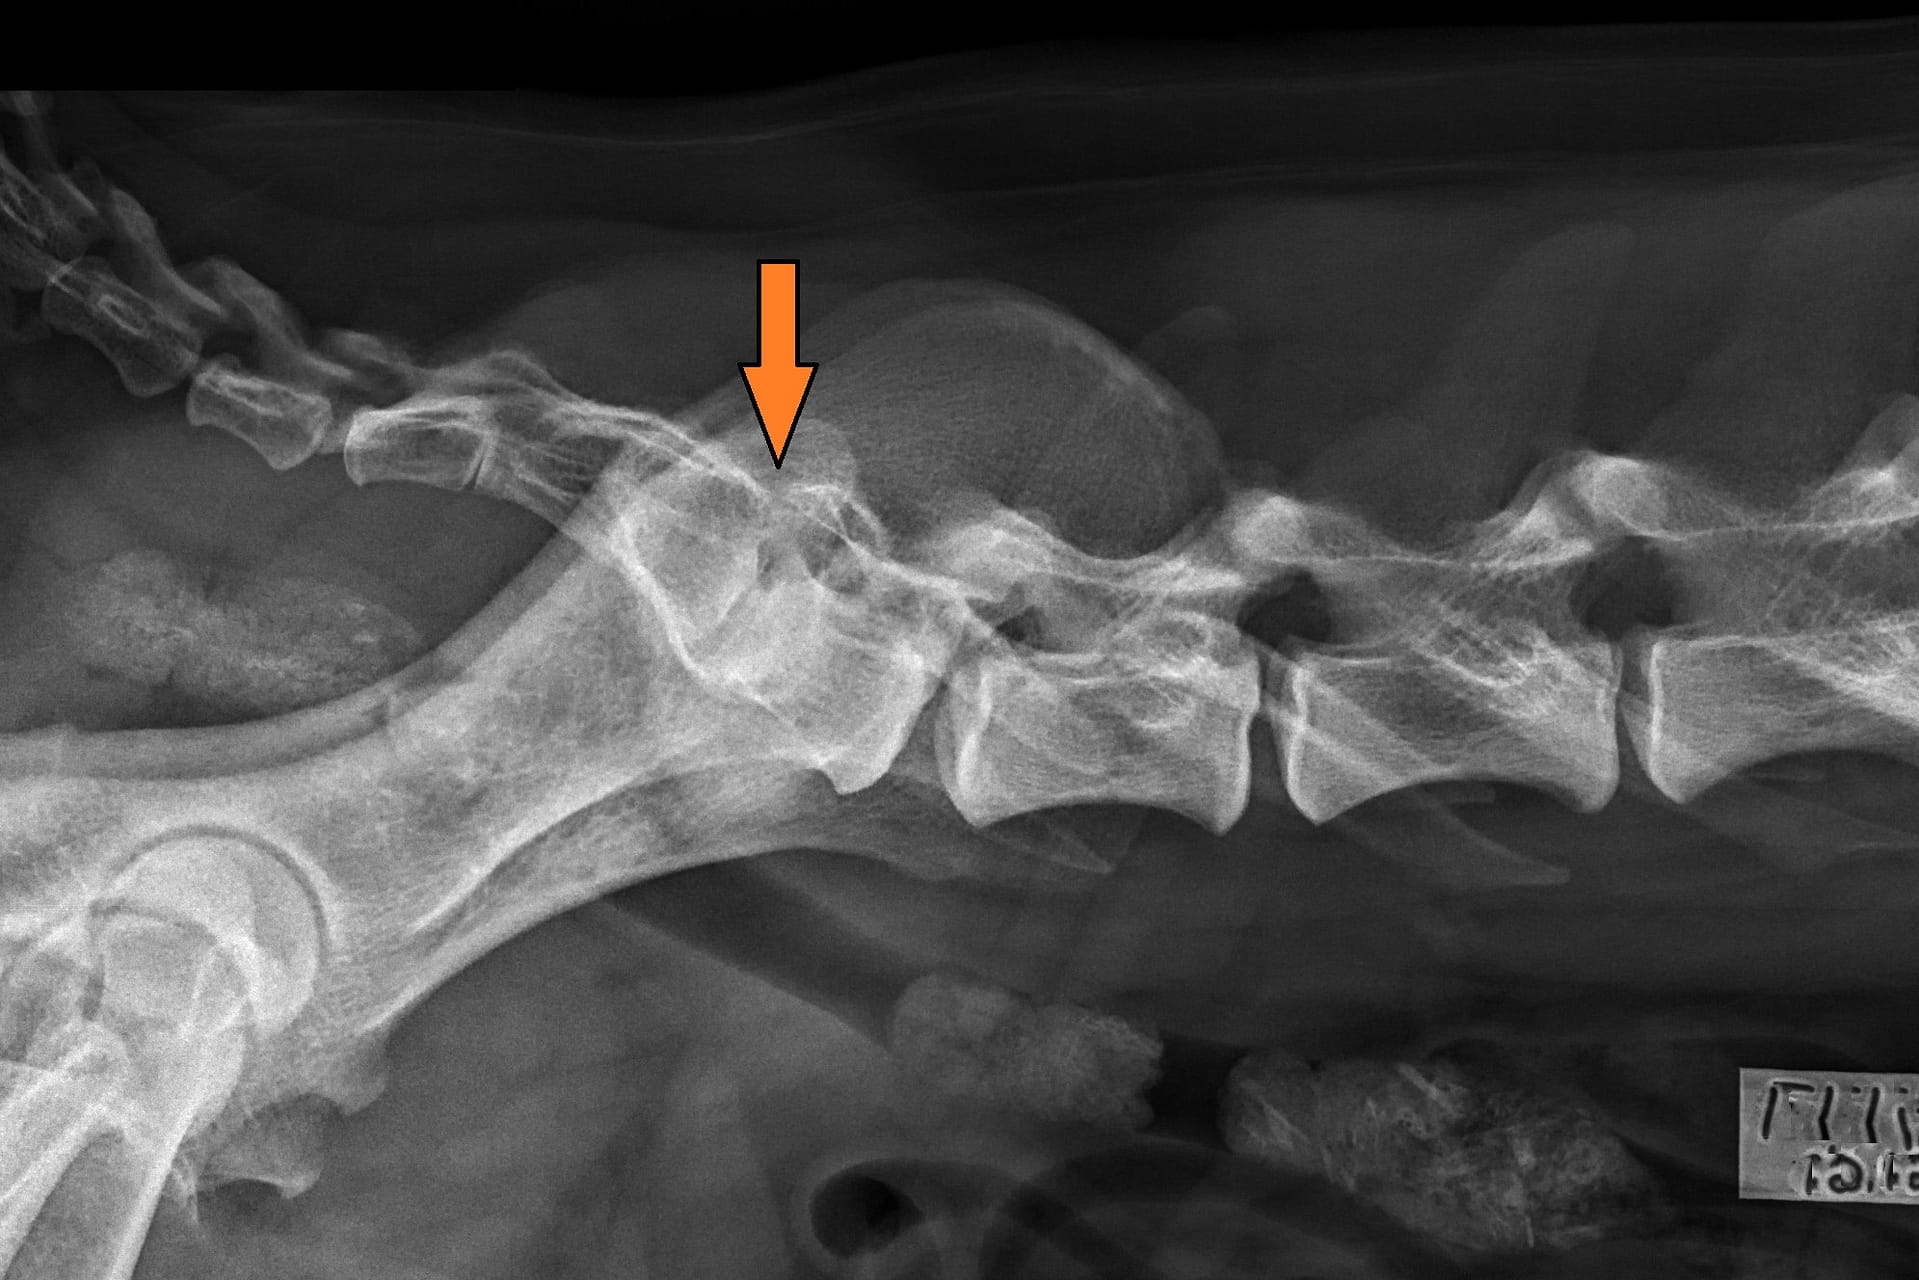

LTV2; symmetrical

LTV3; asymmetrical; on the right in the VD photo the left side of S1 is shaped like a sacral vertebra and on the right side S1 is shaped like a lumbar vertebra including the spinous process.

LTV4; 8 lumbar vertebras. L8 shaped like a lumbar vertebra and it has complete spinous process.